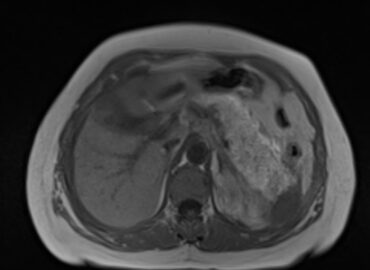

Paciente de sexo femenino de 57 años de edad que acude a consulta por dolor abdominal irradiado hacia el […]